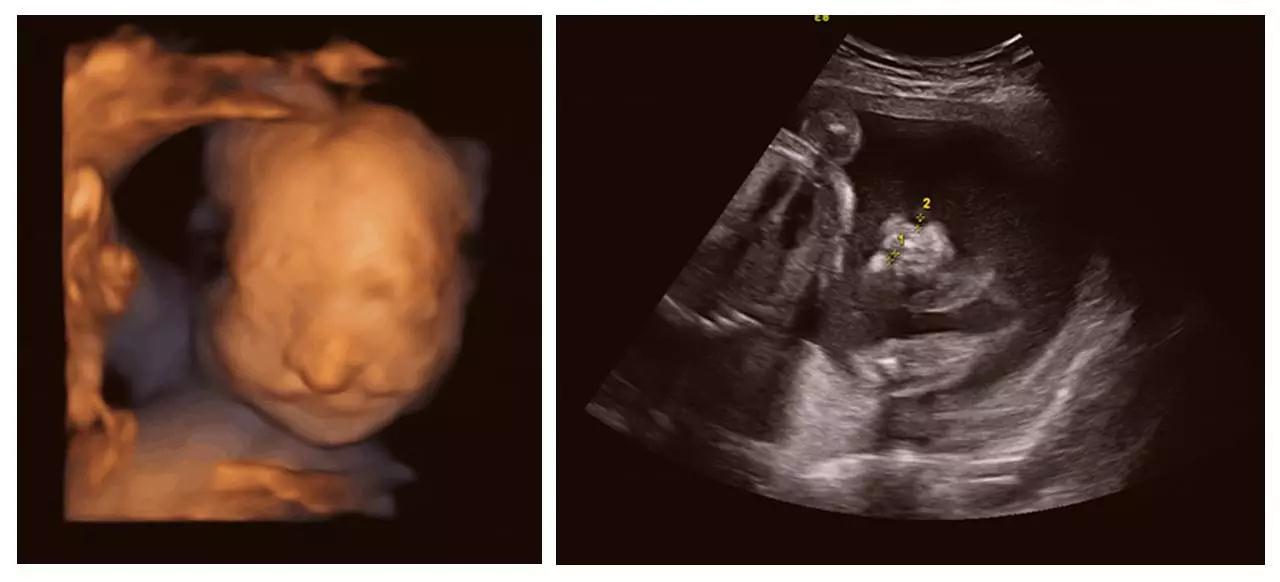

近日,美国对宝宝在妈妈子宫里相拥亲吻的照片在网络疯传。据报道,美国准妈妈Carissa Gill非常期待自己双胞胎女儿们的到来,所以对她们的四维照片特别着迷,而近次孕检,让她有更为惊喜的发现。

在Carissa怀孕25周的次孕检中,她在超声影像(四维彩超)视频中发现,自己的个女儿首先亲吻了另个女儿的胸口,然后她们慢慢接近,后竟然相互用嘴亲吻!

夫妇俩给两个女儿取名为Isabella和Callie。妈妈Carissa把图像照片上传到了社交网站上。她在其中张照片中写道,Isabella在姐姐Callie的脸颊上印了个吻。在另张照片中,她写道,在这刻她很感恩,迫不及待地想要认识这两位珍贵的公主。

正是通过神奇的超声影像(四维彩超),我们起见证了这有爱的幕。超声影像(四维彩超)的出现对于妇产科学界意义重大,在探头下,我们可以清晰地看见宝宝的动态,看见宝宝发育的情况。不仅如此,超声影像(四维彩超)能通过清晰的画面对胎儿的体表进行检查,及早发现唇裂、脊柱裂,大脑、肾、心脏、骨骼发育不良等各种畸形情况,检测和发现各种异常。简单的说,超声影像(四维彩超)的作用,就是从零岁起监测宝宝的发育情况,保障每个新生儿的健康!